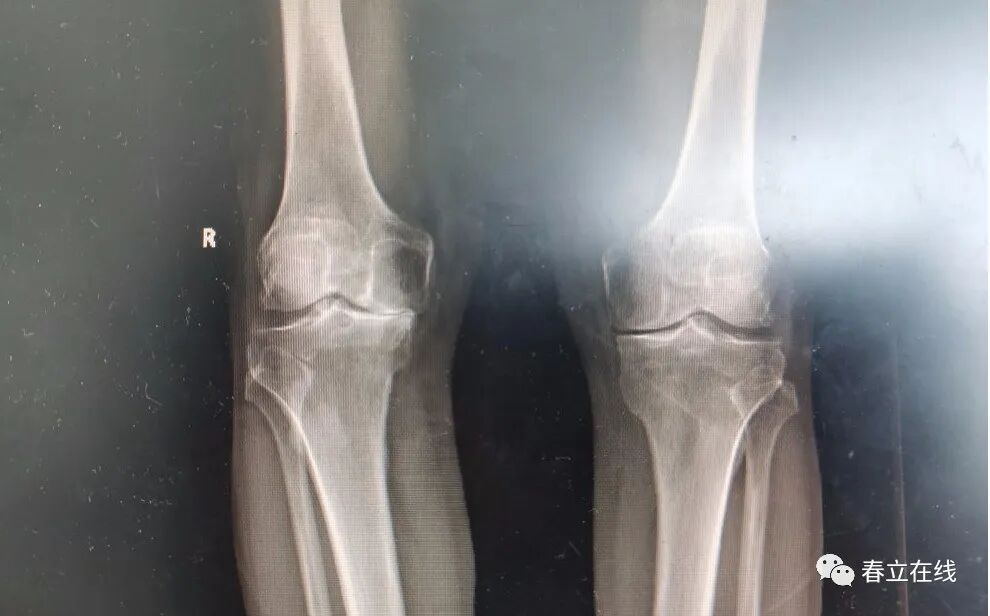

Patient Profile: Yu, Male, 85 years old.

Chief Complaint: Right knee pain with limited mobility for over 10 years, exacerbated in the past month.

Present Illness History: The patient developed right knee pain, swelling and limited mobility more than 10 years ago without obvious cause. The pain was dull and aggravated by movement and stair climbing, which could be relieved by bed rest. The patient did not receive specific treatment. One month ago, he felt the right knee pain gradually worsened, with difficulty in weight-bearing and obvious limping during walking. The pain disturbed his sleep when turning over at night, so he was admitted to our hospital. He was admitted for treatment under the preliminary diagnosis of right knee osteoarthritis in the outpatient department.Physical Examination: Mild varus deformity of the right knee with a range of motion (ROM) of 5–90 degrees. All supplementary examinations were normal. The patient underwent total right knee arthroplasty. He got out of bed and walked on the second day after surgery and was discharged five days postoperatively. A re-examination one month after surgery showed good healing of the knee incision, and the patient was able to walk without a walker. The patient was satisfied with the treatment outcome.

Preoperative photo